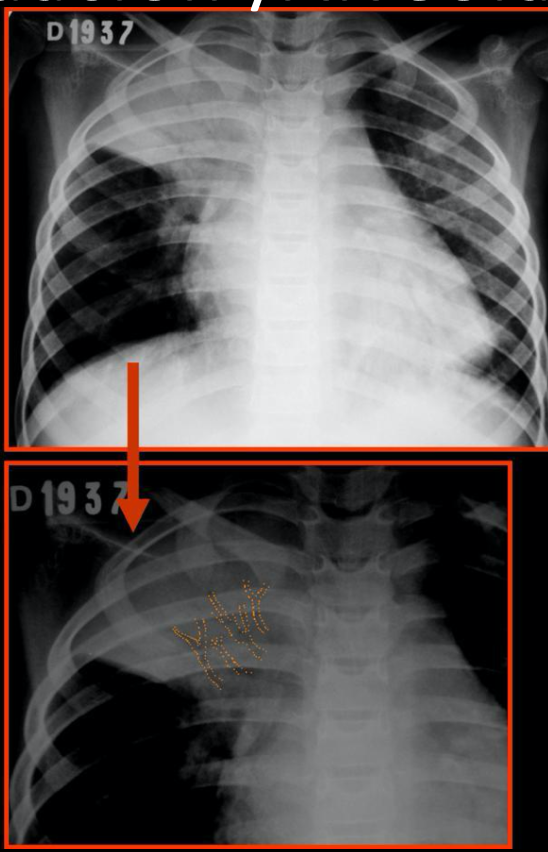

Rx fractura costal

Tórax óseo AP u oblicua

164

Fractura costal